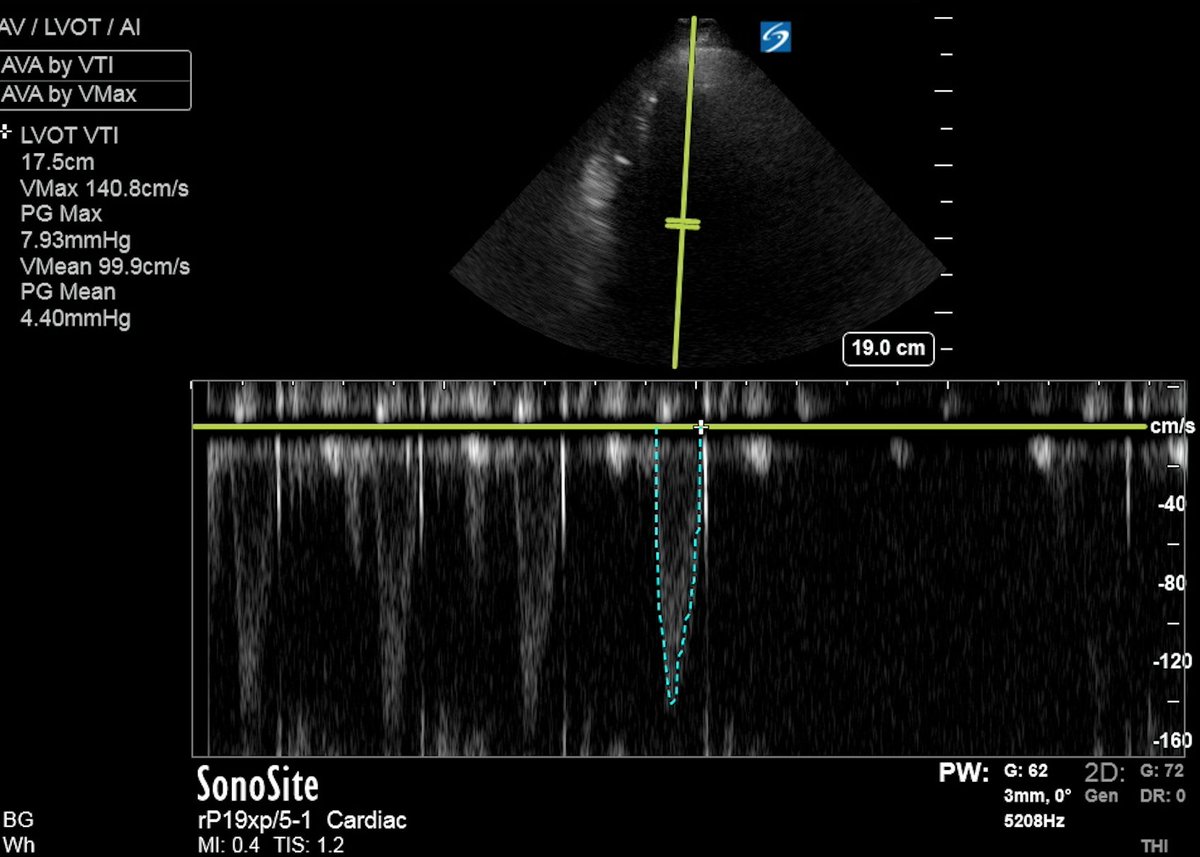

However, pt was oliguric w uop 10 cc/hour. Even though catecholamines are in general contraindicated in this scenario, I decided to try dobutamine drip and see if an ⬆️ in cardiac output would lead to ⬆️ uop. BTW, Vexus was 1. This was the LVOT VTI without and with dobutamine: ImageImage

LVOT VTI increased from ~ 10 to ~17. There was "contractile reserve". This was the impressive change in contractility shown in POCUS. The 4-chamber view: